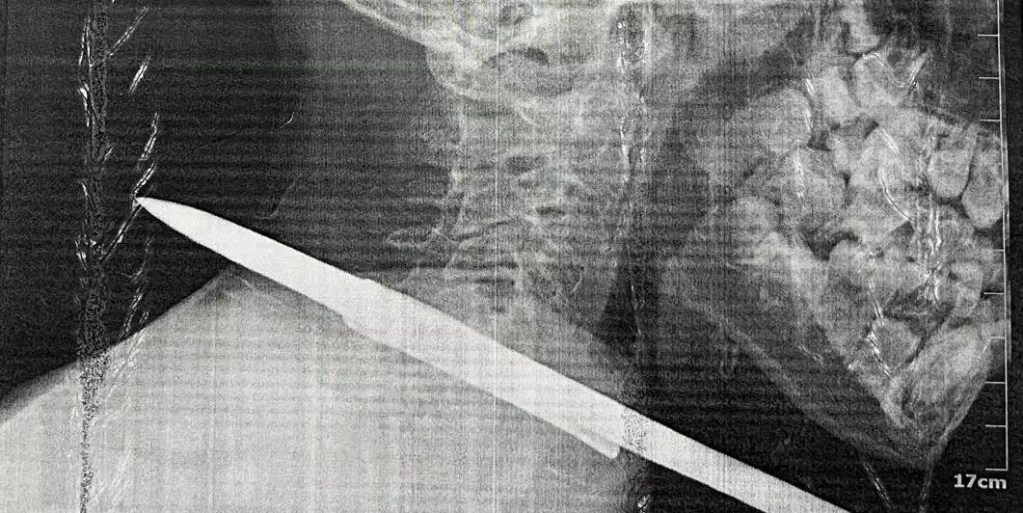

Menino sobreviveu a acidente com arpão de pesca no pescoço em Santarém, no oeste do Pará. (Divulgação / Prefeitura Municipal de Santarém)

Um arpão de pescador foi retirado do pescoço de uma criança de 11 anos após cirurgia no Hospital Municipal de Santarém Dr. Alberto Tolentino Sotelo, na última segunda-feira (07/10), no município de Santarém, na região oeste do Pará. O menino chegou no hospital depois de um acidente grave durante uma pescaria e passou por uma cirurgia de emergência para a retirada do objeto.

No pescoço passam várias estruturas que são muito nobres para o nosso organismo. Passa ali a artéria carótida, a veia jugular, e o arpão estava atravessado a centímetros dessas duas estruturas. Então, por pouco, não foi um acidente muito grave. Foi um milagre”, relatou o médico cirurgião Augusto Aguiar, que fez a retirada de uma vara de arpão que estava atravessada no pescoço do paciente.

O cirurgião Augusto Aguiar, responsável pelo procedimento, analisou que a situação era potencialmente grave dada a localização. A cirurgia foi realizada sem complicações. “A cirurgia foi relativamente simples porque essas estruturas vitais foram poupadas, mas poderia ter sido um desastre. Podemos dizer que um milagre aconteceu ali, porque poderia ter sido uma situação extremamente grave e com potencial risco de vida. Foi um milagre”, enfatizou.